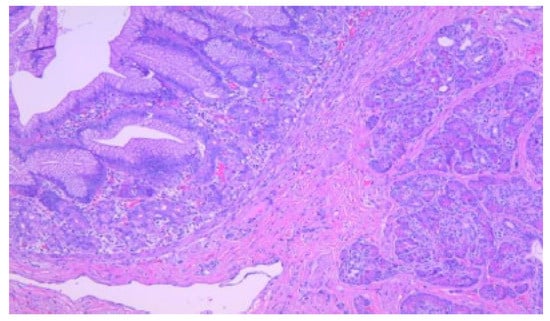

According to the Heinrich classification, modified by Gaspar-Fuentes et al., there are four histological types of EPT: type I—presenting acini, ducts, and islets (complete heterotopia), type II—presenting only ducts (canalicular heterotopia), type III—presenting only acini (exocrine heterotopia), and type IV—presenting only islets (endocrine heterotopia) [19]. 5 out of the 6 cases evaluated belonged to type I and 1 case belonged to type III (Figure 1, Figure 2, Figure 3 and Figure 4).

Figure 3. Duodenal wall with flattened mucosa and pancreatic tissue within the basal part of the mucosa and submucosa, HE, 100×.